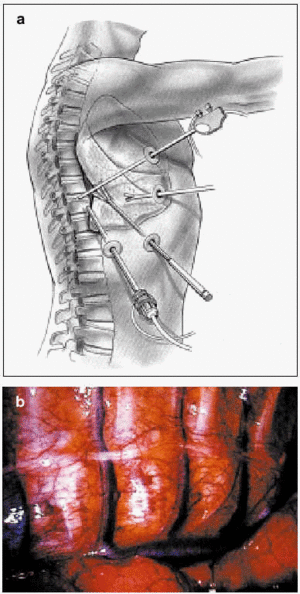

Anterior Approach: Thoracoscopy

Minimal access spinal surgery has been moving forward in recent years and will therefore be covered in more detail in this review. Thoracoscopy (Figure 5) has been introduced as a new therapeutic approach for treating spinal pathology. The endoscope was first used in surgery on the spine in 1993, when it was considered an alternative to "open surgery." At first it was used mainly in patients considered to be at high risk from thoracotomy, given that the minimal procedure is less traumatic for the chest wall.18 Time has shown, however, that the deformity must be elastic and the angle greater than 75º if maximum benefit is to be derived from thoracoscopy. The technique should not be used in patients in whom a lung must be collapsed, who have severe respiratory insufficiency, who require high positive pressures to maintain adequate ventilation, or who have pleural adhesions. For the past 7 years, an anterior endoscopic approach has been used for spinal release surgery (with the purpose of increasing flexibility), for anterior arthrodesis, for epiphysiodesis (to prevent a flat back or the crankshaft problem), and for disk resections. It has also been used to treat certain primary tumors, spinal metastases, and fractured or herniated disks.

Figure 5. An artist's depiction (a) and a surgical image (b) of thoracoscopy.

Thoracoscopy is preferred from the patient's point of view because it is less invasive and causes less pain and morbidity. However, these advantages are less evident to the spinal surgeon. The minimal access approach requires a longer training period, more time in the operating room and often the help of a thoracic or abdominal surgeon. An argument in its favor, however, is the growing interest in shortening hospital stays and decreasing costs.